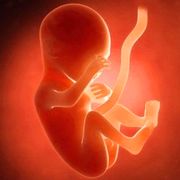

- 胎儿胎儿亲子鉴定亲子鉴定胎儿亲子鉴定是指利用基因技术鉴定胎儿遗传意义上的父亲。当胎儿遗传意义上的父亲是谁不得而知时,产前亲子鉴定可从孕妇的羊水中提取细胞,通过鉴定胎儿的脱氧核糖核酸确认父子关系。胎儿亲子鉴定必须提供的样本为胎儿样本羊水、绒毛

- 胎儿亲子鉴定怎么做,进行胎儿亲子鉴定时,获得胎儿样本的方法通常有以下三种,第一,在怀孕12,14周期间,提取胎儿绒毛组织进行鉴定,第二,在怀孕16,21周期间,抽取3,5ml羊水进行羊水亲子鉴定,第三,在孕8周以上,到宝宝出生前,抽取10